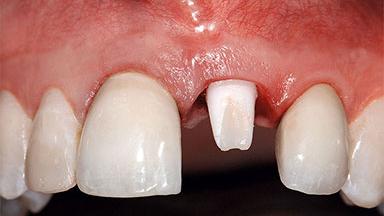

A 63-year-old male patient was referred for a consultation and treatment of partial edentulism in the maxilla. The patient presented with residual anterior teeth and declined a partial removable prosthesis. He reported that the maxillary posterior teeth had been extracted due to mobility and periodontal disease two months before the consultation. The patient’s chief complaint was that his residual maxillary teeth were mobile and that he was unable to chew. The patient’s desire was a stable and comfortable fixed maxillary rehabilitation. The patient was a light smoker (fewer than 10 cigarettes/ day), and his medical history was without significant findings. He was not on any regular medication at the time of consultation. The extraoral examination revealed a normal physiognomy with a correct distribution of the facial thirds. The patient presented a low lip line, and the transition line between teeth and soft tissues was not exposed during a forced smile.